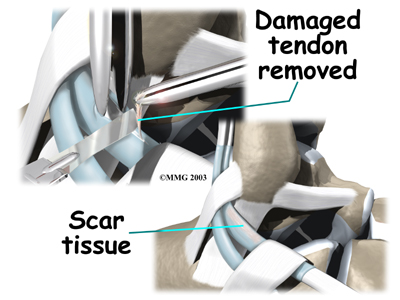

When the lining of the tendon is painful and inflamed (as in tenosynovitis), the goal of surgery is to remove the irritated tissue from around the tendon. This operation is called tendon release. This procedure is done by carefully dividing the tendon sheath that encloses the tendon. Once the , the surgeon around the tendon. The sheath is not stitched back together. The gap in the sheath will eventually fill in with scar tissue. The skin is closed with sutures.

The procedure for surgically treating tendonosis is similar to the method used for tenosynovitis. However, extra measures are taken to thoroughly remove (debride) the degenerated tissue around and within the involved tendon.